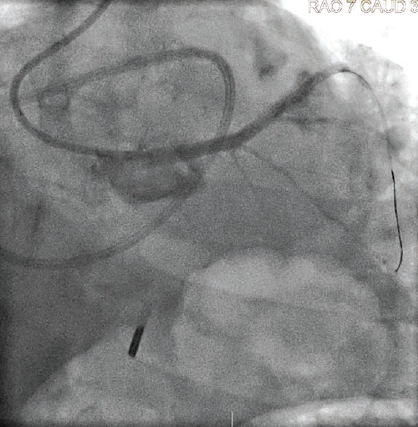

Given the fibrocalcific disease visualized on IVUS, we performed plaque modification with a 3.5 x 15 mm Wolverine cutting balloon (Boston Scientific) with several inflations from the mid LAD to the ostium of the LMCA. IVUS re-assessment demonstrated calcium fracture, indicating the lesion was adequately prepared to accommodate a stent (Figure 4).

We then deployed a 4.0 mm x 24 mm Synergy Megatron stent (Boston Scientific) covering the ostium of the LMCA to the proximal LAD. The mid LAD was treated with 2.75 mm x 15 mm Resolute Onyx stent (Medtronic) deployed just distal to the take-off of the first diagonal branch, with a good final result (Figure 5). Post-stent IVUS demonstrated a minimal stent area of 5.4 mm2 within the mid-LAD stent and 13.7 mm2 within the LMCA (Figure 6).